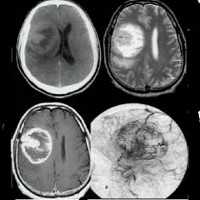

Глиома головного мозга — наиболее распространенная опухоль головного мозга, берущая свое начало из различных клеток глии. Клинические проявления глиомы зависят от ее расположения и могут включать головную боль, тошноту, вестибулярную атаксию, расстройство зрения, парезы и параличи, дизартрию, нарушения чувствительности, судорожные приступы и пр. Глиома головного мозга диагностируется по результатам МРТ головного мозга и морфологического исследования опухолевых тканей. Вспомогательное значение имеет проведение Эхо-ЭГ, ЭЭГ, ангиографии сосудов головного мозга, ЭЭГ, офтальмоскопии, исследования цереброспинальной жидкости, ПЭТ и сцинтиграфии. Общепринятыми способами лечения в отношении глиомы головного мозга являются хирургическое удаление, лучевая терапия, стереотаксическая радиохирургия и химиотерапия.

Наиболее приемлемым способом диагностики глиомы головного мозга на сегодняшний день является МРТ головного мозга. При невозможности ее проведения может применяться МСКТ или КТ головного мозга, контрастная ангиография мозговых сосудов, сцинтиграфия. ПЭТ головного мозга дает сведения о метаболических процессах, по которым можно судить о скорости роста и агрессивности опухоли. Кроме того, с диагностической целью возможно проведение люмбальной пункции. При глиоме головного мозга анализ полученной цереброспинальной жидкости выявляет наличие атипичных (опухолевых) клеток.

Кровоизлияние в желудочки головного мозга ( вентрикулярная геморрагия , внутрижелудочковое кровоизлияние )

При подозрении на кровоизлияние в желудочки головного мозга пациента нужно как можно скорее доставить в больницу. Не исключено, что в машине скорой помощи ему придется проводить реанимацию. В условиях стационара для подтверждения диагноза пациенту проводят: МРТ или КТ головного мозга, анализ крови с подсчетом количества тромбоцитов, исследуют коагулограмму, осуществляют мониторинг ЭКГ и АД.